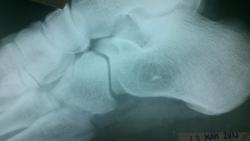

Пациент 36 лет. Обратился в травмпункт через неделю после травмы- падение с высоты. Ударился пяткой.

Остеоид-остеома, может и асептический некроз.

травматических костных повреждений нет. образование пяточной кости-случаная попутная находка, больше похоже на остеохондрому. и это никак не асептический некроз.

А какова дальнейшая тактика? Что рекомендовать такому пациенту? Я нашла в литературе, что возможно озлокачествление.